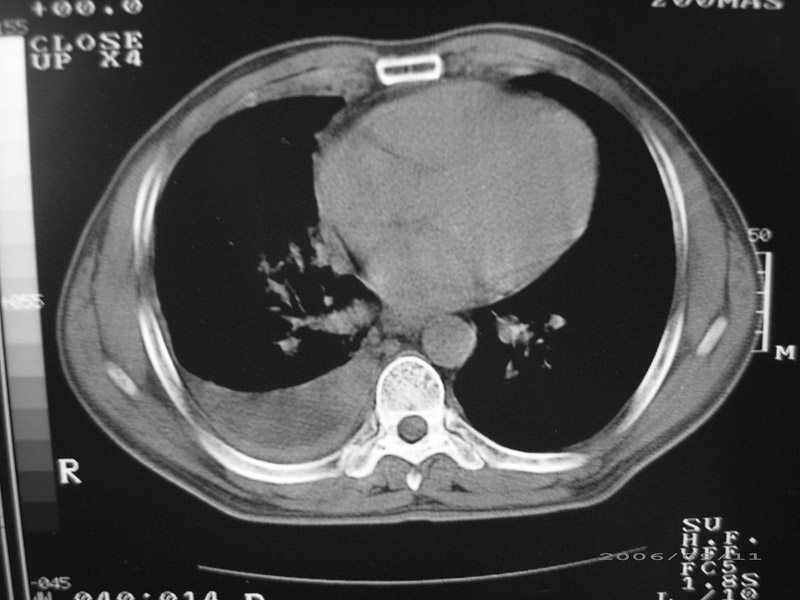

以下是引用守望可可西里在2006-9-11 15:29:00的发言:[br][br] ct平扫表现:右侧胸膜腔缩小,积液,胸膜增厚且不均匀、不规则,以纵隔胸膜增厚为主,边缘呈锯齿状,并见附壁内突之结节状肿块影。右肺含气量减少,纹理聚集,右肺门中下部见数个肿大的淋巴结。纵隔无移位,内未见明显肿大淋巴结,双侧主支气管以及各叶、段支气管比较通畅。。[br] 考虑:右侧胸膜恶性间皮瘤,伴肺门淋巴结转移。